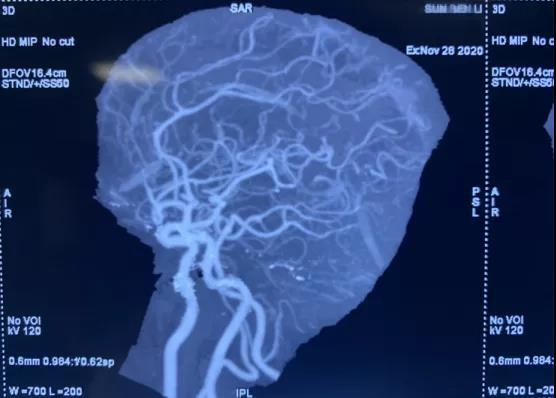

動脈瘤診斷金標準為:數字減影血管造影(DSA) ,于學利主任親自把關,盛國良、楊德森等神經外科醫(yī)師立刻以頭部CTA為基礎,急診行顱內血管造影術,術中明確了動脈瘤的形態(tài)、大小、指向、周圍臨近血管關系。